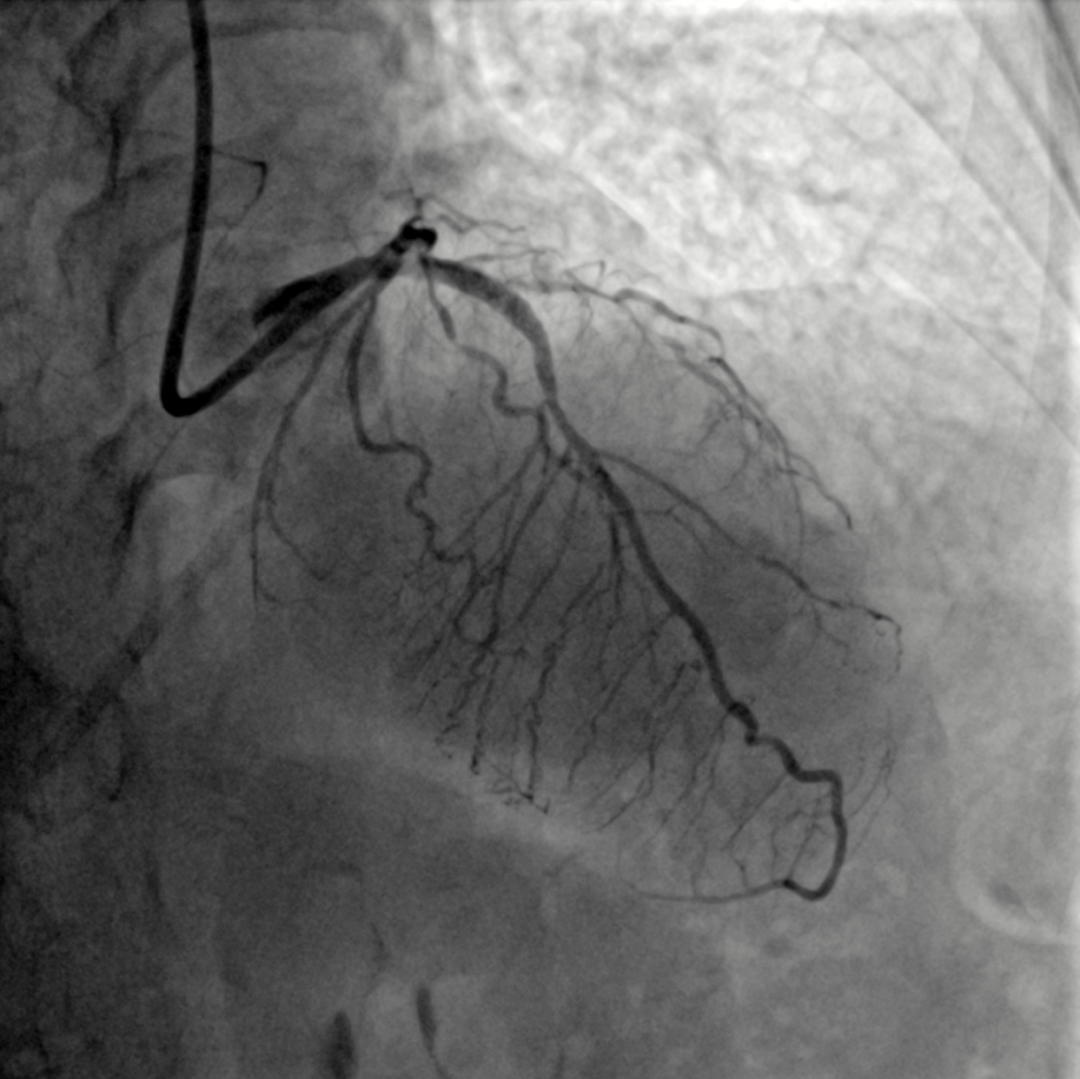

经过充分的术前准备,术前OCT检查提示:前降近中段钙化病变处可见90-360°环形钙化,钙化厚度约0.38mm-0.6mm,长度约10mm,局部可见钙化小结。较厚的环形钙化是导致上次手术使用高压球囊及切割球囊无法顺利打开病变的原因。针对病变特点,在OCT的精确定位下,启用3.5x12mm Shockwave冲击波球囊技术在环形钙化处精准震荡扩张,启动脉冲发生器,持续激发脉冲10S,可见球囊逐渐膨胀充分,随后以6atm扩张震波球囊,可见球囊扩张满意。重新定位冲击波球囊,重复脉冲3个周期共4个周期脉冲优化震波碎裂疗效,复查OCT清楚可见环形钙化斑块碎裂松解,局部未见明显夹层,获得较大管腔,满足支架植入条件。成功于左前降支近段植入3.5mm*13mm药物洗脱支架1枚。

手术耗时约40分钟,并顺利完成前降支支架植入。术后患者症状缓解,并于近日出院。

Shockwave球囊充分预处理后,顺利植入支架